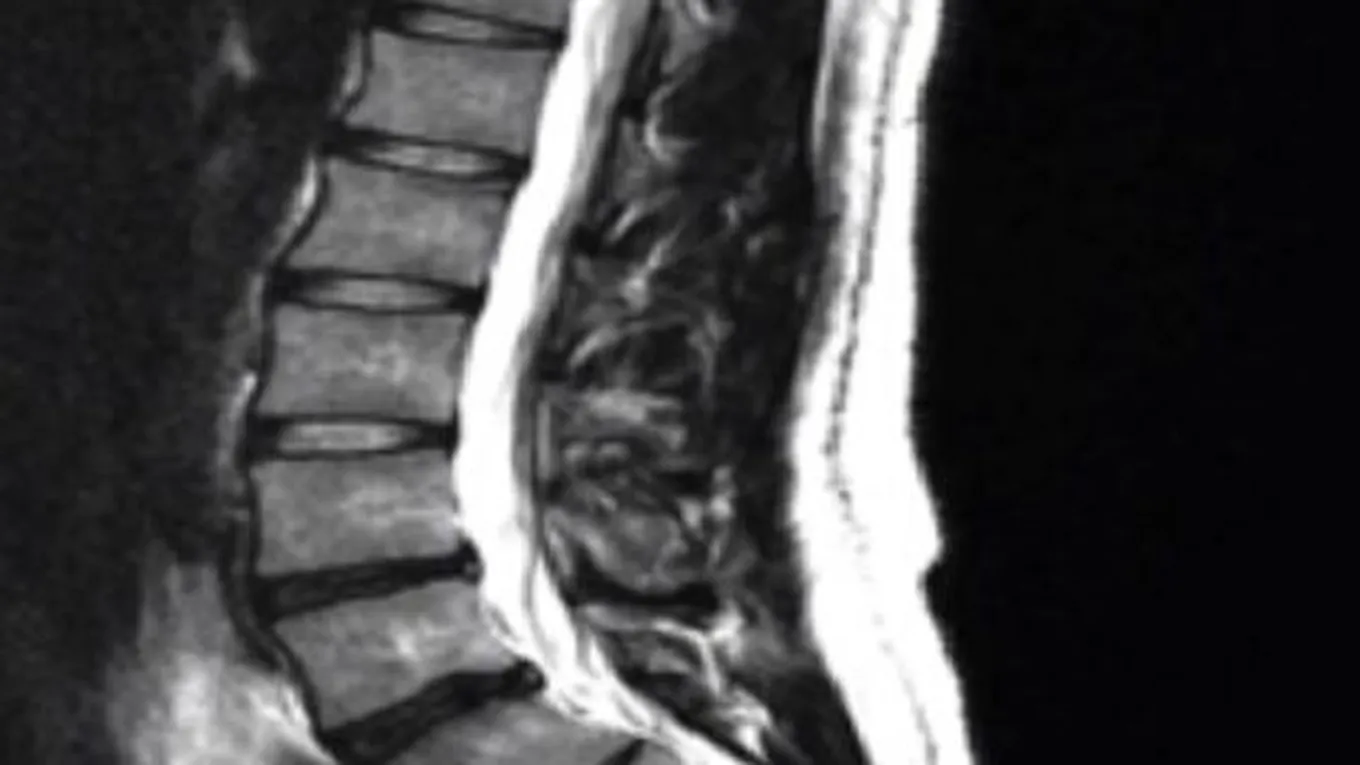

- الانزلاق الغضروفي : يعرف الانزلاق الغضروفي بأنّه نتوء يحدث في الأقراص الغضروفية الموجودة بين فقرات العمود الفقري، وذلك بسبب وجود تلف في الألياف المحيطة بها، مما يسبب بروز للمادة الهلامية، الأمر الذي يشكل ضغط على الأعصاب المقابلة لها، وهذا ما يسبب الشعور بالألم الشديد، ومن أكثر الأشخاص عرضة بالإصابة بمرض الانزلاق الغضروفي هم الأشخاص الذين يعانون من السمنة، وأولئك المعتادون على حمل الأشياء الثقيلة، والكبار في السن .